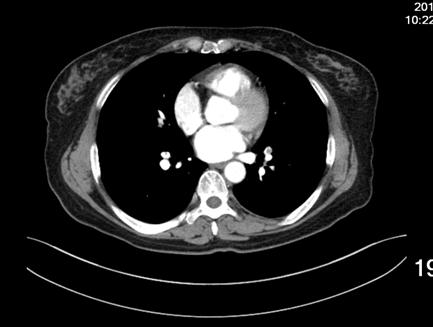

患者女性,52岁,因右膝关节疼痛,活动受限三十年入院。既往无高血压等慢性病史,无静脉血栓栓塞症病史,无慢性静脉瓣功能不全病史。诊断:右膝半月板损伤,骨关节炎。术前排除手术禁忌,于CSEA下行右膝关节镜下探查清理,半月板成形术。手术过程顺利,手术使用止血带,手术时间25分钟,失血约10ml。术后24小时患者下床后出现头晕、头迷、气短、冷汗、扶墙晕倒于墙边,给予心电血氧监护,血压:78/45mmHg,心率:118次/分,指脉血氧饱和度:78%,急检指尖血糖:6.4,血浆D-二聚体:1247ug/L,心肌酶谱及肌钙蛋白未见明显异常,术后2天夜晚再次出现头晕,头迷,气短,冷汗等症状,给予吸氧等治疗后症状缓解,检查肺增强CT(图1),示患者多发肺动脉栓塞,行双下肢静脉彩超检查,示右小腿肌间血栓,左小腿肌间静脉扩张(图2)。术后第3天于局麻下行经皮下腔静脉滤器置入术后,转入呼吸科行继续治疗。

1增强肺动脉CT:多发性肺动脉栓塞。